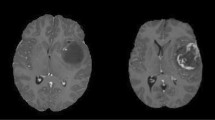

This imaging system is not limited to TBI studies; we have used in it variety of applications in our lab utilizing transgenic mice and injectable fluorescent dyes18,19. The system can be shortened to obtain images from the cortex in mice by omission of the window and direct attachment of the GRIN lens to a glass cover slip. For instance, microglia become activated and mediate secondary damage in the penumbra region surrounding the ischemic core after stroke13. To determine if our system could be used to detect morphological features of activation after experimental ischemic stroke, we used the filament model of middle cerebral artery occlusion (MCAo)17 in Cx3cr1-tdTomato mice that express red fluorescent protein in microglia. Three weeks after implantation, baseline images were acquired and then mice were imaged 24 hours after 60-minutes of ischemia followed by reperfusion (I/R). Baseline images showed microglia with long ramified processes characteristic of the resting state (Fig. 6a,b, baseline). After I/R, we observed microglia with brushy processes and ameboid morphology that is indicative of the activated state (Fig. 6a, 24 hrs post-I/R). In contrast, sham-injured mice did not have any features of activated microglia (Fig. 6b). In addition, cellular dynamics, such as activated microglia moving through tissue and monocytes and neutrophils flowing through a blood vessel can be recorded after MCAo (Video S1). These results demonstrate the utility of the hrGRIN system for use in murine models of inflammation and for evaluation of drugs to treat inflammation-mediated secondary damage after ischemic stroke.

Representative images at baseline and 24 hours after sham or transient (60 minute) MCAo procedure. Microglia in the resting state have ramified processes, as seen in both baseline conditions (Baseline a,b) and in the sham injured mouse (Sham, b). When microglia become activated, their processes retract and the cells often exhibit a brushy or ameboid morphology (24 hr post-I/R, a). Insets are enlarged, representative images of microglia (caret) morphology. Images are z-projections of 5 × 1 µm optical slices. Scale bar denotes 10 µm, inset scale bar denotes 5 µm.